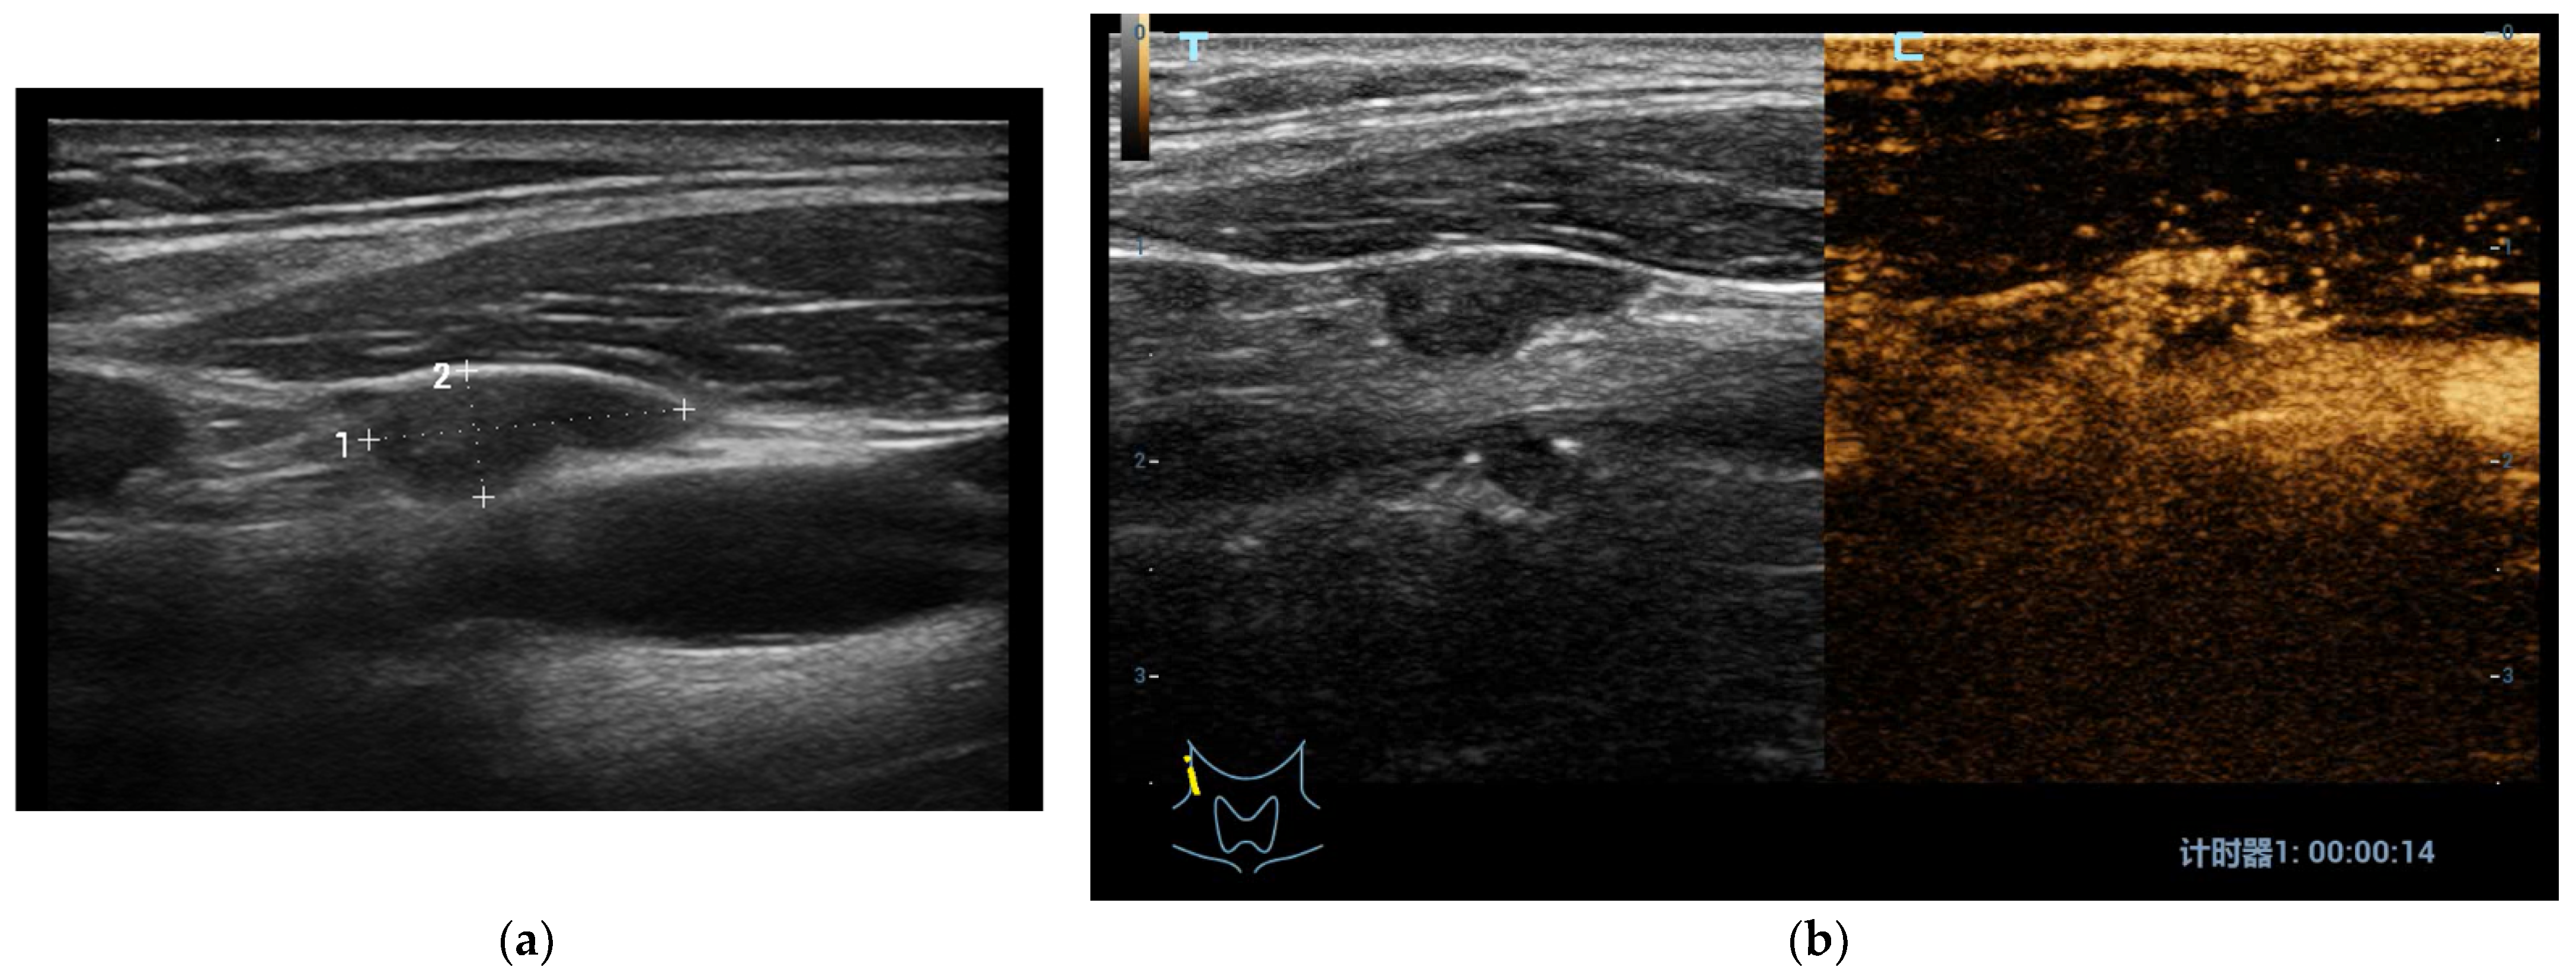

3.2.1. Benign Nodules

- Zhang, L.; Zhou, W.; Zhan, W. Role of ultrasound in the assessment of percutaneous laser ablation of cervical metastatic lymph nodes from thyroid carcinoma. Acta Radiol. 2018, 59, 434–440. [Google Scholar] [CrossRef]

- Ma, S.; Zhou, P.; Wu, X.; Tian, S.; Zhao, Y. Detection of the Single-Session Complete Ablation Rate by Contrast-Enhanced Ultrasound during Ultrasound-Guided Laser Ablation for Benign Thyroid Nodules: A Prospective Study. Biomed Res. Int. 2016, 2016, 9565364. [Google Scholar] [CrossRef] [Green Version]